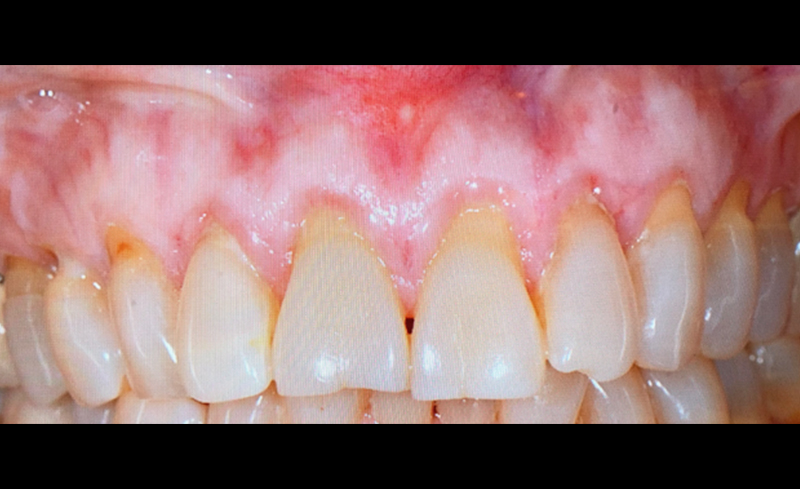

| 年齢 | 38歳女性 |

|---|---|

| 主訴 | 数本の歯が揺れはじめたことを理由に来院 |

| 治療内容 | プラークや歯石に伴い赤く腫れた歯茎が認められます(左図)。歯周病の基本的な治療に加え、一部外科処置を行い、5年が経過しました(右図)。適切なメンテナンスにより歯の揺れもなくなりました。 |

| 治療期間 | 約5年間 |

上の二枚は初診時。大きな歯石(赤マル)が大量に歯根面に沈着し、それに伴い骨の吸収が認められます(青矢印)。下の二枚が5年後。骨の吸収が止まり一部骨再生が認められます(緑矢印)。